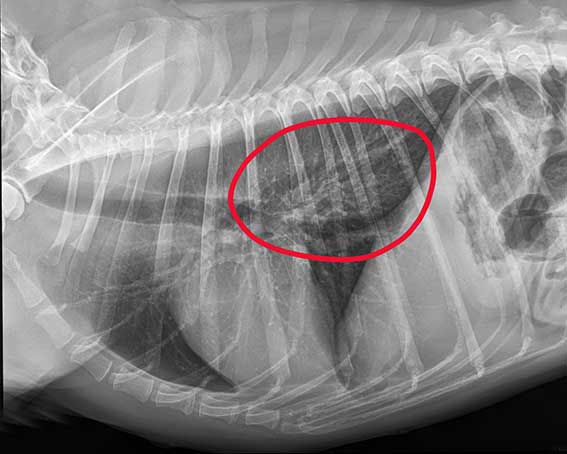

Nach der erfolgreichen Endoskopie: Fremdkörper entfernt, keine Hinweise auf Verletzungen der Speiseröhre.

Nach der erfolgreichen Endoskopie zeigte sich die Speiseröhre vom Fremdkörper deutlich gereizt und gerötet. Es waren schon kleinere innere Blutungen sichtbar. Die abschließende Röntgenkontrolle bestätigte aber: Glücklicherweise keine Luft im Brustkorb, keine erkennbaren Risse in der Speiseröhre. Gia erhielt schmerzlindernde und magenschützende Medikamente und durfte schon am Sonntagmorgen wieder nach Hause.